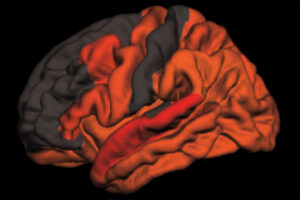

Poor sleep has long been linked with Alzheimer’s disease, but researchers have understood little about how sleep disruptions drive the disease. Now, studying mice and people, researchers at Washington University School of Medicine in St. Louis have found that sleep deprivation increases levels of the key Alzheimer’s protein tau. And, in follow-up studies in the […]